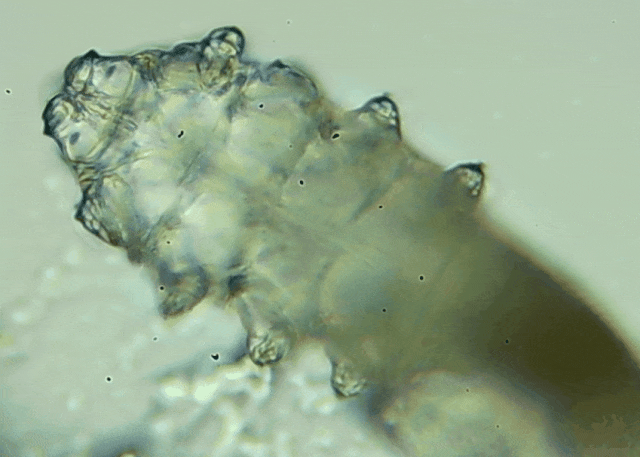

蠕形螨是一類肉眼看不見的寄生螨,常見的有毛囊蠕形螨和皮脂蠕形螨,常駐在人類的毛囊和皮脂腺里,尤其是眼睛的瞼板腺和睫毛根部。數(shù)量少時,蠕形螨能與人體“和平共處”,但一旦你免疫力下降、油脂分泌旺盛或清潔不到位,他們就會以你難以想象的速度瘋狂繁殖。

睫毛上驚現(xiàn)80只螨蟲!【文章導讀】我只是眼睛癢,結果醫(yī)生說我睫毛里有80只蟲?這不是恐怖片,而是真實的病例:武漢一13歲男孩,右眼9根睫毛里檢出39只螨蟲,左眼9根里檢出47只。 而且這不是極端個案,廈門眼科中

而且這不是極端個案,廈門眼科中心干眼門診的臨床數(shù)據(jù)統(tǒng)計,眼睛經(jīng)常紅癢發(fā)炎的人群,多數(shù)都有螨蟲,約80%以上的瞼緣炎患者螨蟲超標,一根睫毛最多能有幾十只。